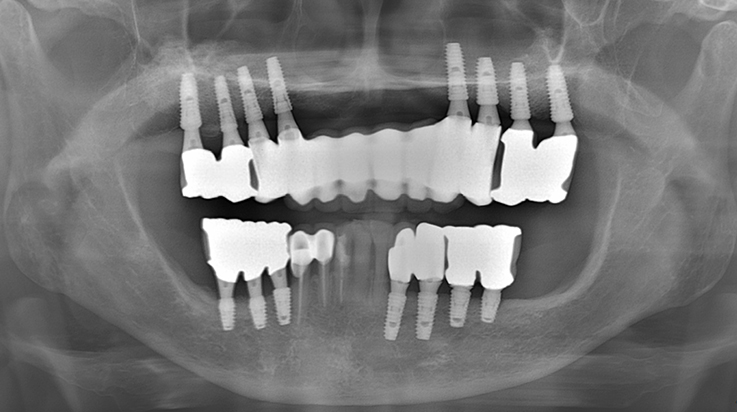

Fully edentulous clinical cases